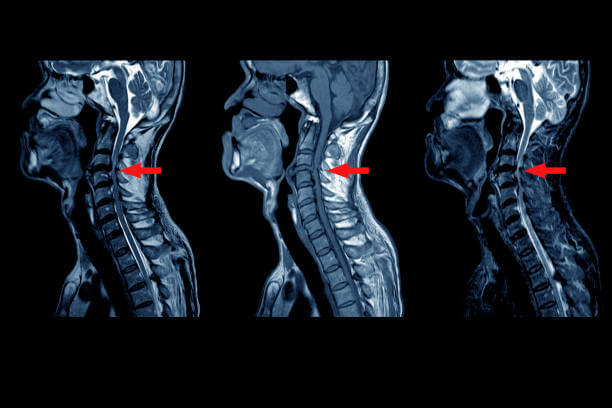

경추 추간판 탈출증

경추 손상은 경추 추간판 탈출증을 의심할 수 있는데, 이는 목뼈와 뼈 사이의 추간판이 제자리를 벗어나고 신경이 눌려 있음을 의미합니다.

과거에는 노화로 인해 많이 발생했지만 현대에는 많은 사람들이 어릴 때부터 컴퓨터 등 전자기기에 노출되어 잘못된 자세와 습관이 형성되고 일자목과 거북목의 모양이 일찍 보이는 경우가 많습니다.

C자 곡선을 유지해야 하는 목 부분은 점차 일자 모양으로 바뀌어 곧은 목이 되는 경우가 많습니다. 이 경우 외부의 충격을 분산시키기 어려워지고, 반복되는 행동습관으로 인해 목뼈가 휘어진 상태에서 배열이 이루어지기 쉽습니다.

그 결과 특정 부위에 하중이 집중되면서 디스크가 돌출되거나 퇴행성 질환을 유발할 수 있습니다.